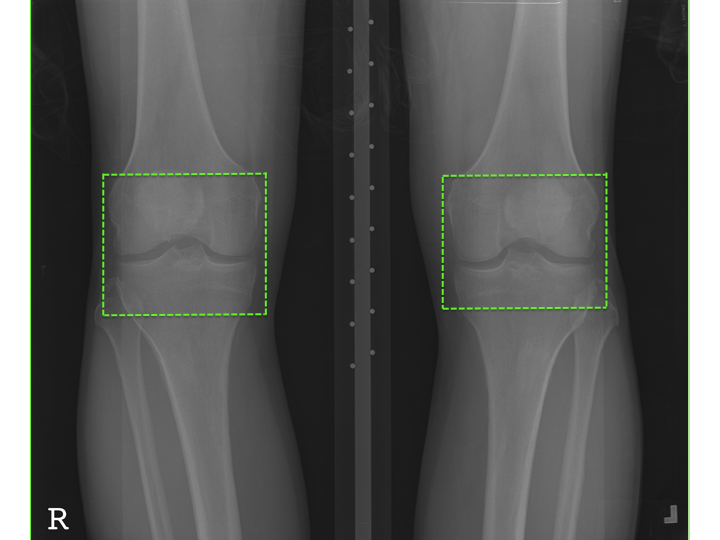

The data used for the experiments and analysis in this study are bilateral PA fixed flexion knee X-ray images. Figure 3 shows some samples of knee X-ray images from the dataset. Due to variations in X-ray imaging protocols, there are some visible artefacts in the X-ray images (Figure 3).

Refer to caption

Figure 3: Samples of bilateral PA fixed flexion knee OA radiographs.

Classification of knee OA images and the assessment of severity conditions can be achieved by examining the characteristic features of knee OA: variations in the joint space width and the osteophytes (bone spurs) formations in the knee joints [6]. Radiologists and medical practitioners examine only the knee joint regions in the X-ray images to assess knee OA. Hence, the region of interest (ROI) for classifying knee OA images is only the knee joint regions (left and right knees). Figure 6 shows the ROI in a X-ray image. The author believes that it is better to focus on the ROI instead of the entire X-ray image for accurate classification and this is also computationally economical. For these reasons, automatically detecting and extracting the knee joint regions from the X-ray images becomes an essential pre-processing step, before classification.

Figure 6: A knee OA X-ray image with the region of interest: the knee joints.